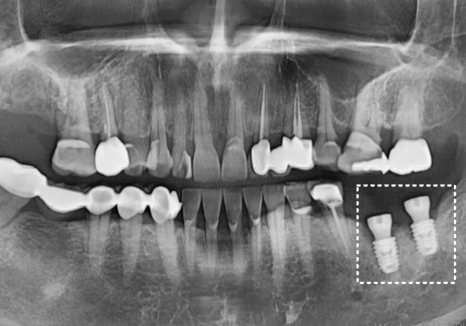

염증의 근원인 기존 임플란트 뿌리를

깨끗하게 제거하고,

다행히 남은 뼈의 상태를 고려하여

당일 즉시 새로운 임플란트 식립을 도와드렸습니다.

그로부터 약 3개월 후,

임플란트 뿌리와 잇몸뼈가

단단하게 하나로 굳어진 것을 확인한 뒤,

강도와 심미성이 뛰어난 지르코니아 보철물을

올려 치료를 마무리해 드렸습니다. ^^